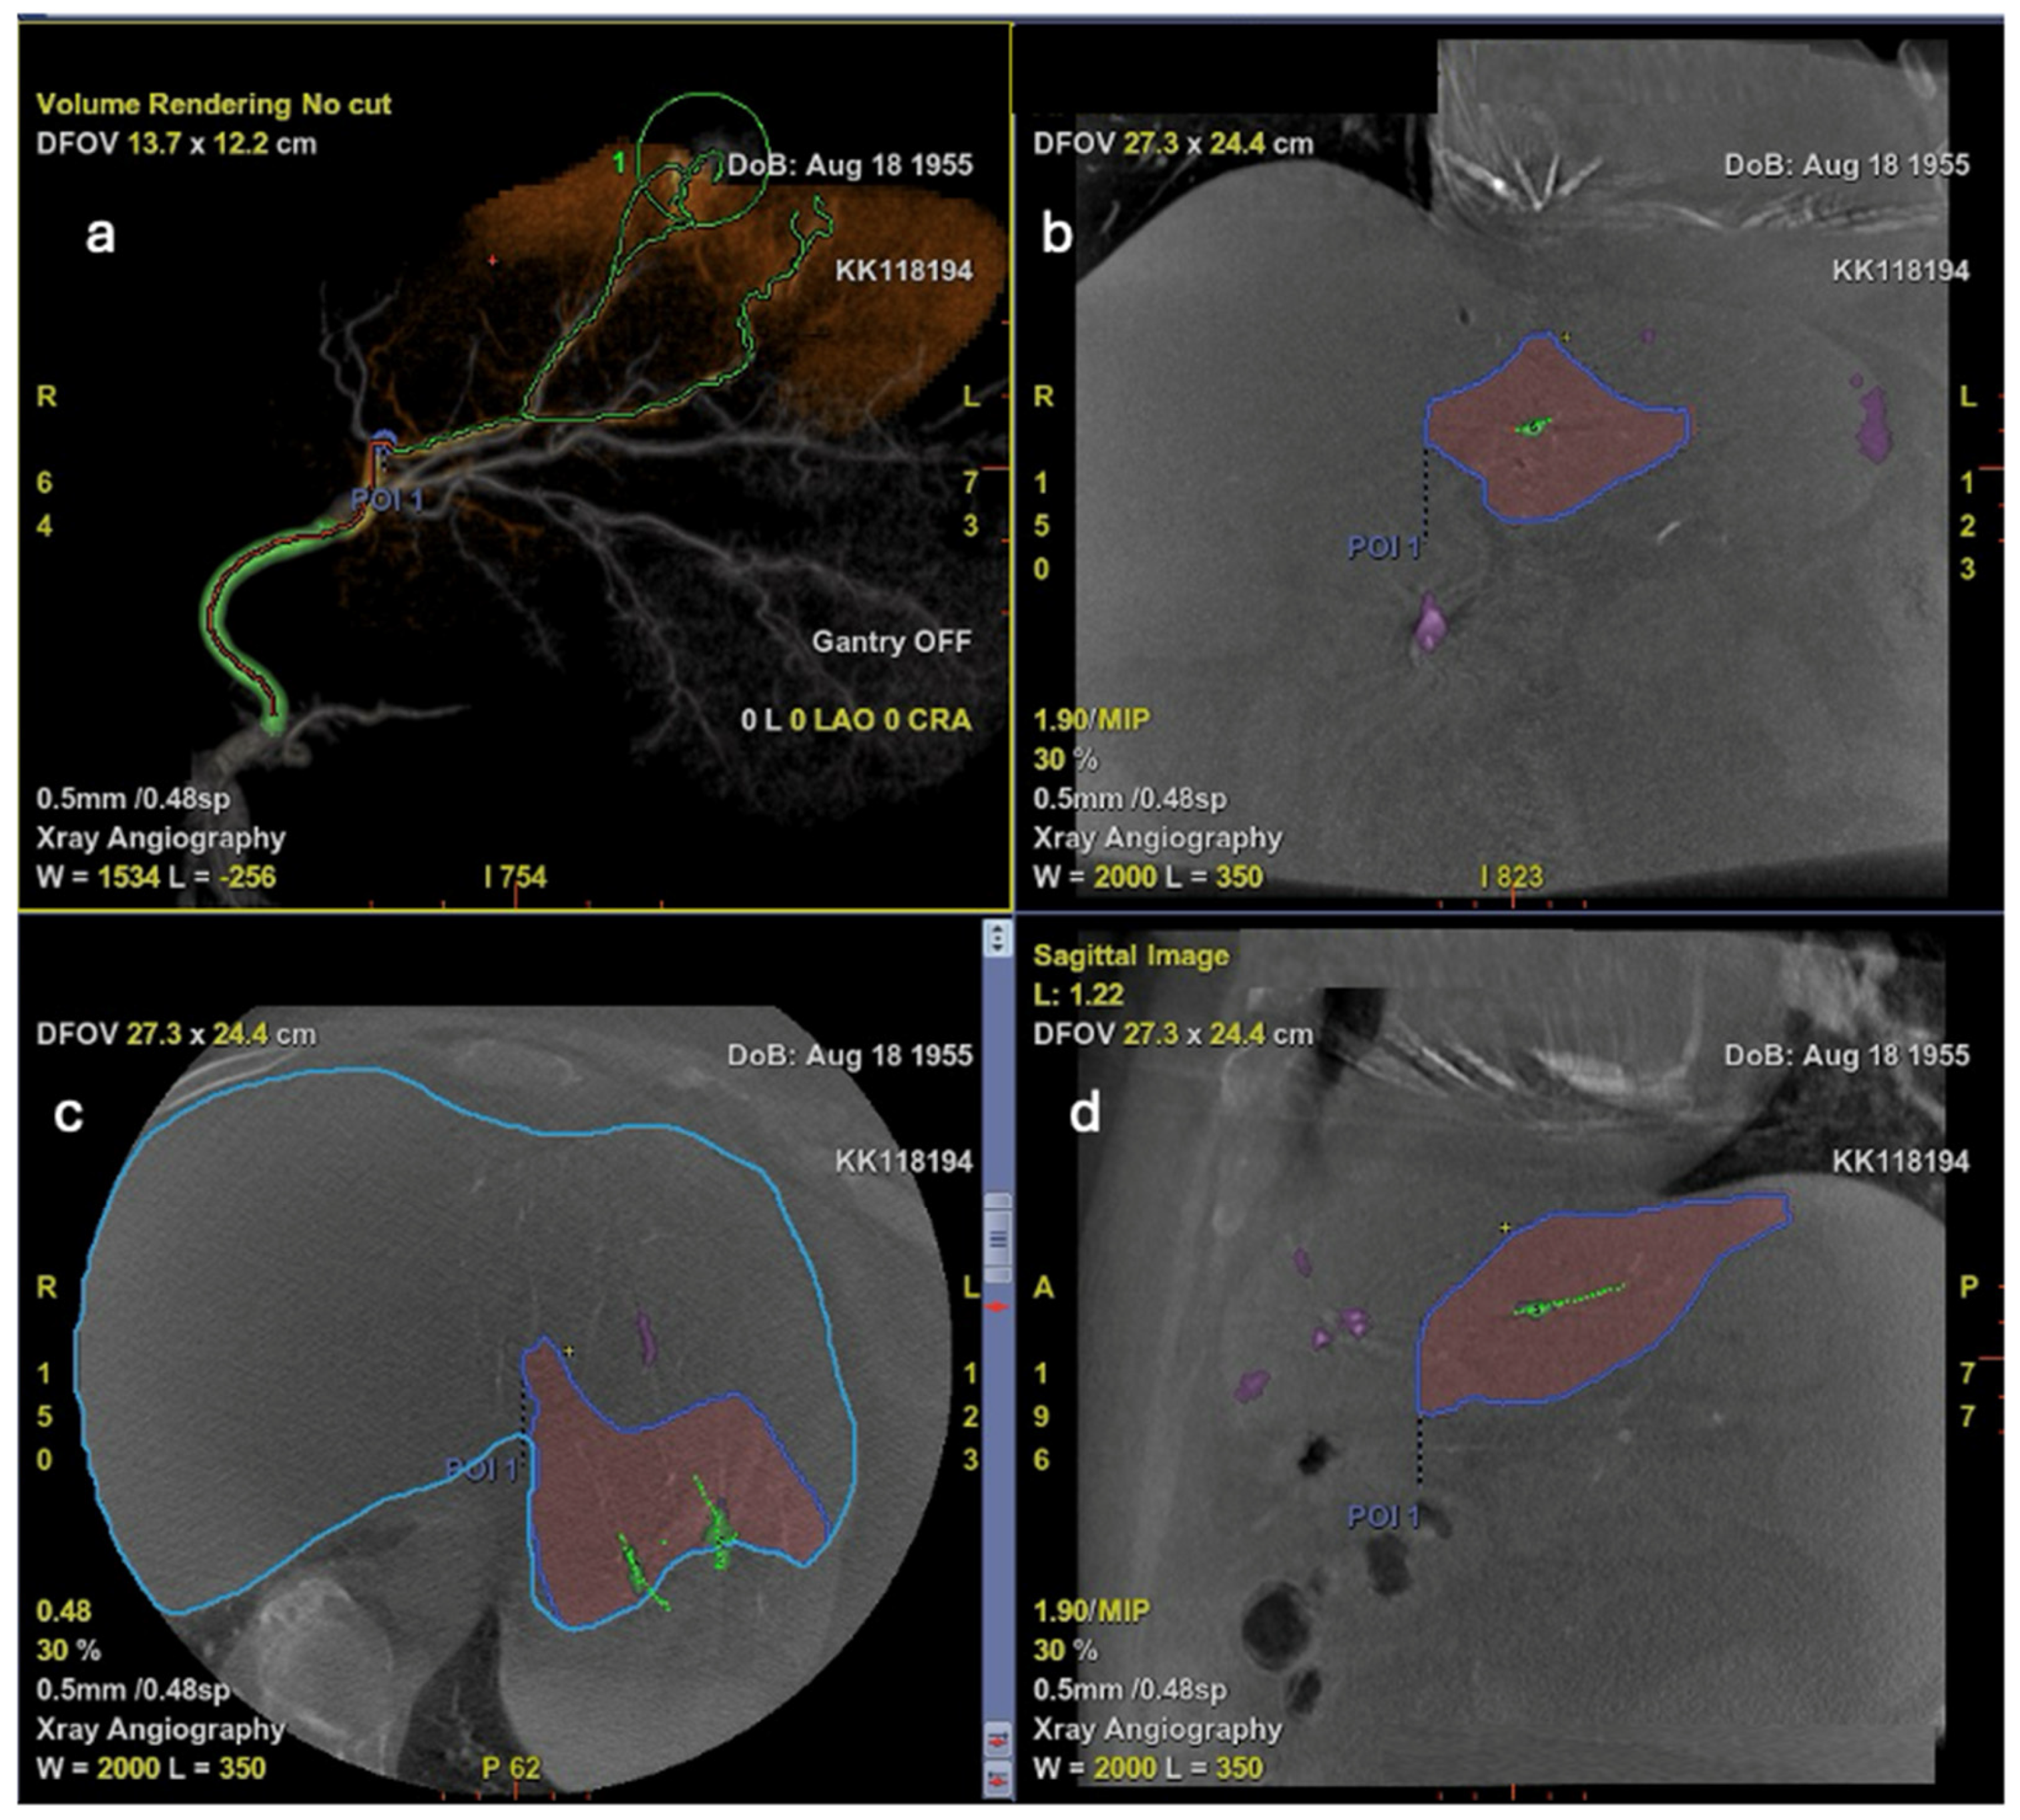

7. Additive Role of Artificial Intelligence

- Automatically extract and reconstruct the hepatic arterial tree;

- Highlight potential tumor feeders, even when overlying vessels obscure direct visualization;

- Provide a “virtual roadmap” for catheter trajectory planning.